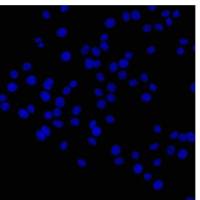

病理染色(油红染色 大体油红 HE染色 Masson染色 天狼星红染色 TTC染色 包埋 切片)